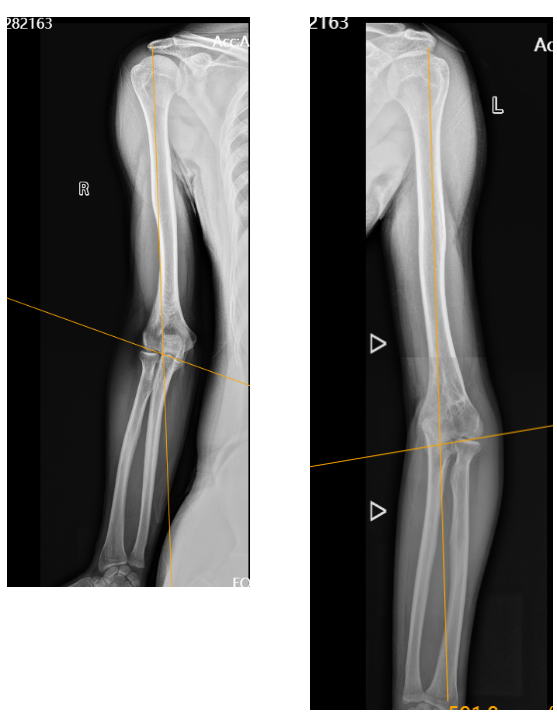

当小磊还是个10岁的孩子时,随父母到草原骑马不小心摔了下来,导致肱骨髁上骨折,在当地医院经历了手术治疗,术后就发现胳膊弯了(肘内翻畸形),但因并不影响活动就一直没管也没在意。随着渐渐长大,小磊却发现“胳膊弯了”这个问题让他很困扰,左上肢用不上力,干不了一点儿重活。更让人糟心的事也发生了,就在7个月前,小磊又摔伤了。这次直接导致肘关节骨折合并脱位,在当地医院进行手法整复石膏固定治疗。然而,一用力胳膊弯外侧就会突出,桡骨小头就向后外侧滑出、不稳定,导致肘关节不能用力。当地医院并不具备这种损伤的手术技术,他们推荐小磊到成人ai

中午12:30,查晔军院长会议一结束就赶来病房了解小磊的情况,询问了他的病史,查看了他大老远带来的之前就诊的影像资料。查晔军院长根据小磊的病情变化详细规划了手术方案。由于手术的特殊性,专门从北京定制了一个“手术利器”——个性化打印截骨导板。此时此刻,困扰小磊20多年的顽疾终于有了解决方案。

5天后,一场河南省首例治疗复杂肘关节疾病的手术在成人ai 高新院区手术室开展:个性化定制3D打印截骨导板辅助肘内翻截骨矫形+外侧副韧带重建,治疗肘关节不稳定。定制的3D打印截骨导板与患者的肱骨外髁完全贴合,大大缩短手术时间,做到精准截骨、精确复位。术中,肱骨截骨钢板内固定后发现胳膊变直了,但是桡骨头仍不稳定,外侧关节囊破损,按术前计划进行了肘关节外侧副韧带重建,恢复肘关节外侧稳定性,防止肘关节活动时桡骨头向外后方脱位。1个半小时,手术顺利结束。

内蒙小伙小磊一直觉得“胳膊弯了”,其实是肘内翻畸形,通常由于先天或后天因素造成尺骨轴线向内侧偏移,携物角<0°,这种情况一般有两种临床表现:肘部畸形和功能障碍。肘部畸形,即在肘关节损伤经治疗后(或未经治疗),出现肘关节伸直位,内翻角明显增大,严重者可达15°~35°,此时肘后三角关系改变,外髁与鹰嘴之间的距离加宽。功能障碍,肘关节一般活动可基本正常,但均有不同程度肌力减弱。